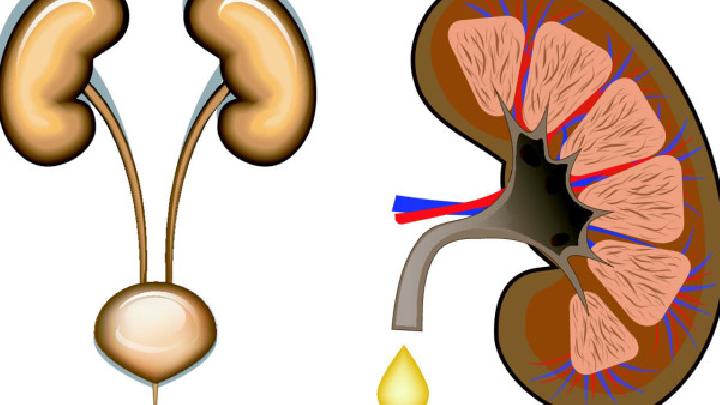

1.局部与远处复发 通常认为,远处转移是再外科手术之禁忌证。但这也不是绝对的,有一些病例可以采用新辅助治疗方法使无法切除的远处转移灶变为可以切除者,同样可以得到再次手术的机会。对存在局部多处复发患者,在有的诊疗中心可进行局部多处病灶的切除术。但因其有较高的手术死亡率,故在不具备手术经验的医院,则不宜勉为其难,可视为手术禁忌证。 对于有症状的局部多处复发患者,一般认为已无法根治性切除。姑息性手术却不能提高生存率,但仅用降低死亡率的观点来评估外科手术切除的疗效是不恰当的。有些姑息性切除可提高患者生活质量和解除其疼痛症状。为解除症状而进行的外科手术治疗只需切除大块复发的肿瘤组织。放疗联合化疗因可以解除疼痛、降低出血、提高生活质量,故通常是姑息性手术术后的常用方法。盆腔血管的选择性化疗对不可切除的肿瘤有减瘤作用。如果复发病灶接近肛门,就需要用腔内支架或结肠造口术。对有出血症状的患者,其他可选择的治疗方法还有激光消融、电烧灼和血管栓塞。局部切除对于会阴复发者,可选择腹会阴联合直肠切除术,但可导致盆腔扩散且预后不良。 3.可切除的局部复发  晚期患者包括盆腔周围侧壁肿瘤浸润、髂血管受累导致下肢水肿、双侧输尿管梗阻导致双侧肾盂积水、坐骨神经受侵犯导致双下肢肌无力、肿瘤侵犯坐骨切迹及腹主动脉周围淋巴结转移等。局限的盆腔侧壁侵犯和S2以上的骶骨侵犯,因为充分切除的可能性很小,被认为是相对禁忌证。 关于切除的信息 子宫切除手术多用于切除子宫肿瘤及某些子宫出血和附件病变等,经腹部切除子宫切除术的操作法,子宫切除术后护理很重要,因为子宫切除术不是一个太小的手术,会对身体造成一定的损伤。  任何手术,包括子宫肌瘤手术都是对患者身体有一定危害的,因此也要尽量避免。是否需要进行子宫肌瘤手术需要根据患者的实际情况来决定,这里我们就简单为您介绍一下吧。  类风湿性关节炎是一种对患者身体危害非常大的疾病,有很多患者因为多年深受这种疾病的折磨从而想到了手术切除,但是这些患者也担心切除后还会复发,所以今天就这个问题我们来了解一下,类风湿性关节炎切除后会复发吗?  女性两侧大阴唇的后面各有一黄豆大小的腺体,该腺体有长约1~2厘米的腺管,开口于小阴唇与处女膜之间的沟内,这个腺体,医学上称为“前庭大腺”。因其生理特点,前庭大腺炎切除病灶后仍然有一定的复发率,因此,保持外阴清洁是预防感染可防止复发的主要方法。  胃癌切除手术后后背经常痛怎么回事?胃癌可能会出现周围组织侵袭和转移的情况,如果出现背部疼痛的情况就要考虑可能和胃癌的脊柱转移有关,针对这种情况要及时到当地医院进行复查,根据转移的情况给予相应的治疗措施,所以胃癌是可以出现背部疼痛的。  前列腺癌睾丸切除手术多少钱,很多肿瘤晚期都会发生转移,前列腺癌也不例外。约有三分之一甚至三分之二的前列腺癌患者在初次就医时就已有淋巴结转移,多发生在骼内、骼外、腰部、腹股沟等部位。可引起相应部位的淋巴结肿大及下肢肿胀。血行转移多见于骨骼(如骨盆、骶骨、腰椎、股骨上段等〉和内脏(如肺、肝、脑、肾上腺、睾丸等)。所以患病就要及时治疗,但是很多人不知道前列腺癌治疗要花多少钱,下面就由小编详细的为您介绍,前列腺癌睾丸切除手术多少钱。  骨癌切除后还会复发吗?部分骨癌患者在手术后还会出现病情恶化或者复发的情况,患者很不明白这是怎么回事,骨癌复发对人体的危害很大,因此要注意预防,这对治疗效果有很大的帮助,而且还能让患者摆脱骨癌的困扰,和正常人一样生活。  近几年胆囊息肉的患者越来越多,据临床统计显示,其中产生癌变的大约有12%,所以为了预防胆囊息肉发生癌变,患者们一定要积极进行治疗。目前胆囊息肉最有效的治疗方法当属手术治疗,手术可分为保胆取息和胆囊切除两种方式,由于胆囊切除多少会对身体产生一些不利影响,并且不是所有患者都需要行胆囊切除术,因此患者们一定要三思而后行。  有时候,人们在进行疾病治疗方面,对于引起该类疾病的原因是模糊的,因此在治疗方面不能很好地展开。对于子宫肌瘤此类常见妇科疾病,广大女性朋友也不是很清楚其病因,在治疗方面也是比较困难的,下面小编就为大家介绍子宫肌瘤是怎么引起的?  肝癌是如今世界上对人类健康危害最大的恶性肿瘤之一,对于早期肝癌病人和病人家属来说,希望明确的第一个问题就是:肝癌早期切除后能治愈吗?就目前治疗现状而言,肝癌仍然是医学上未被攻克的一大难题,然而这也并不等于得了肝癌就被宣判了死刑,临床上亦有许多治疗后长期生存的病例。 |